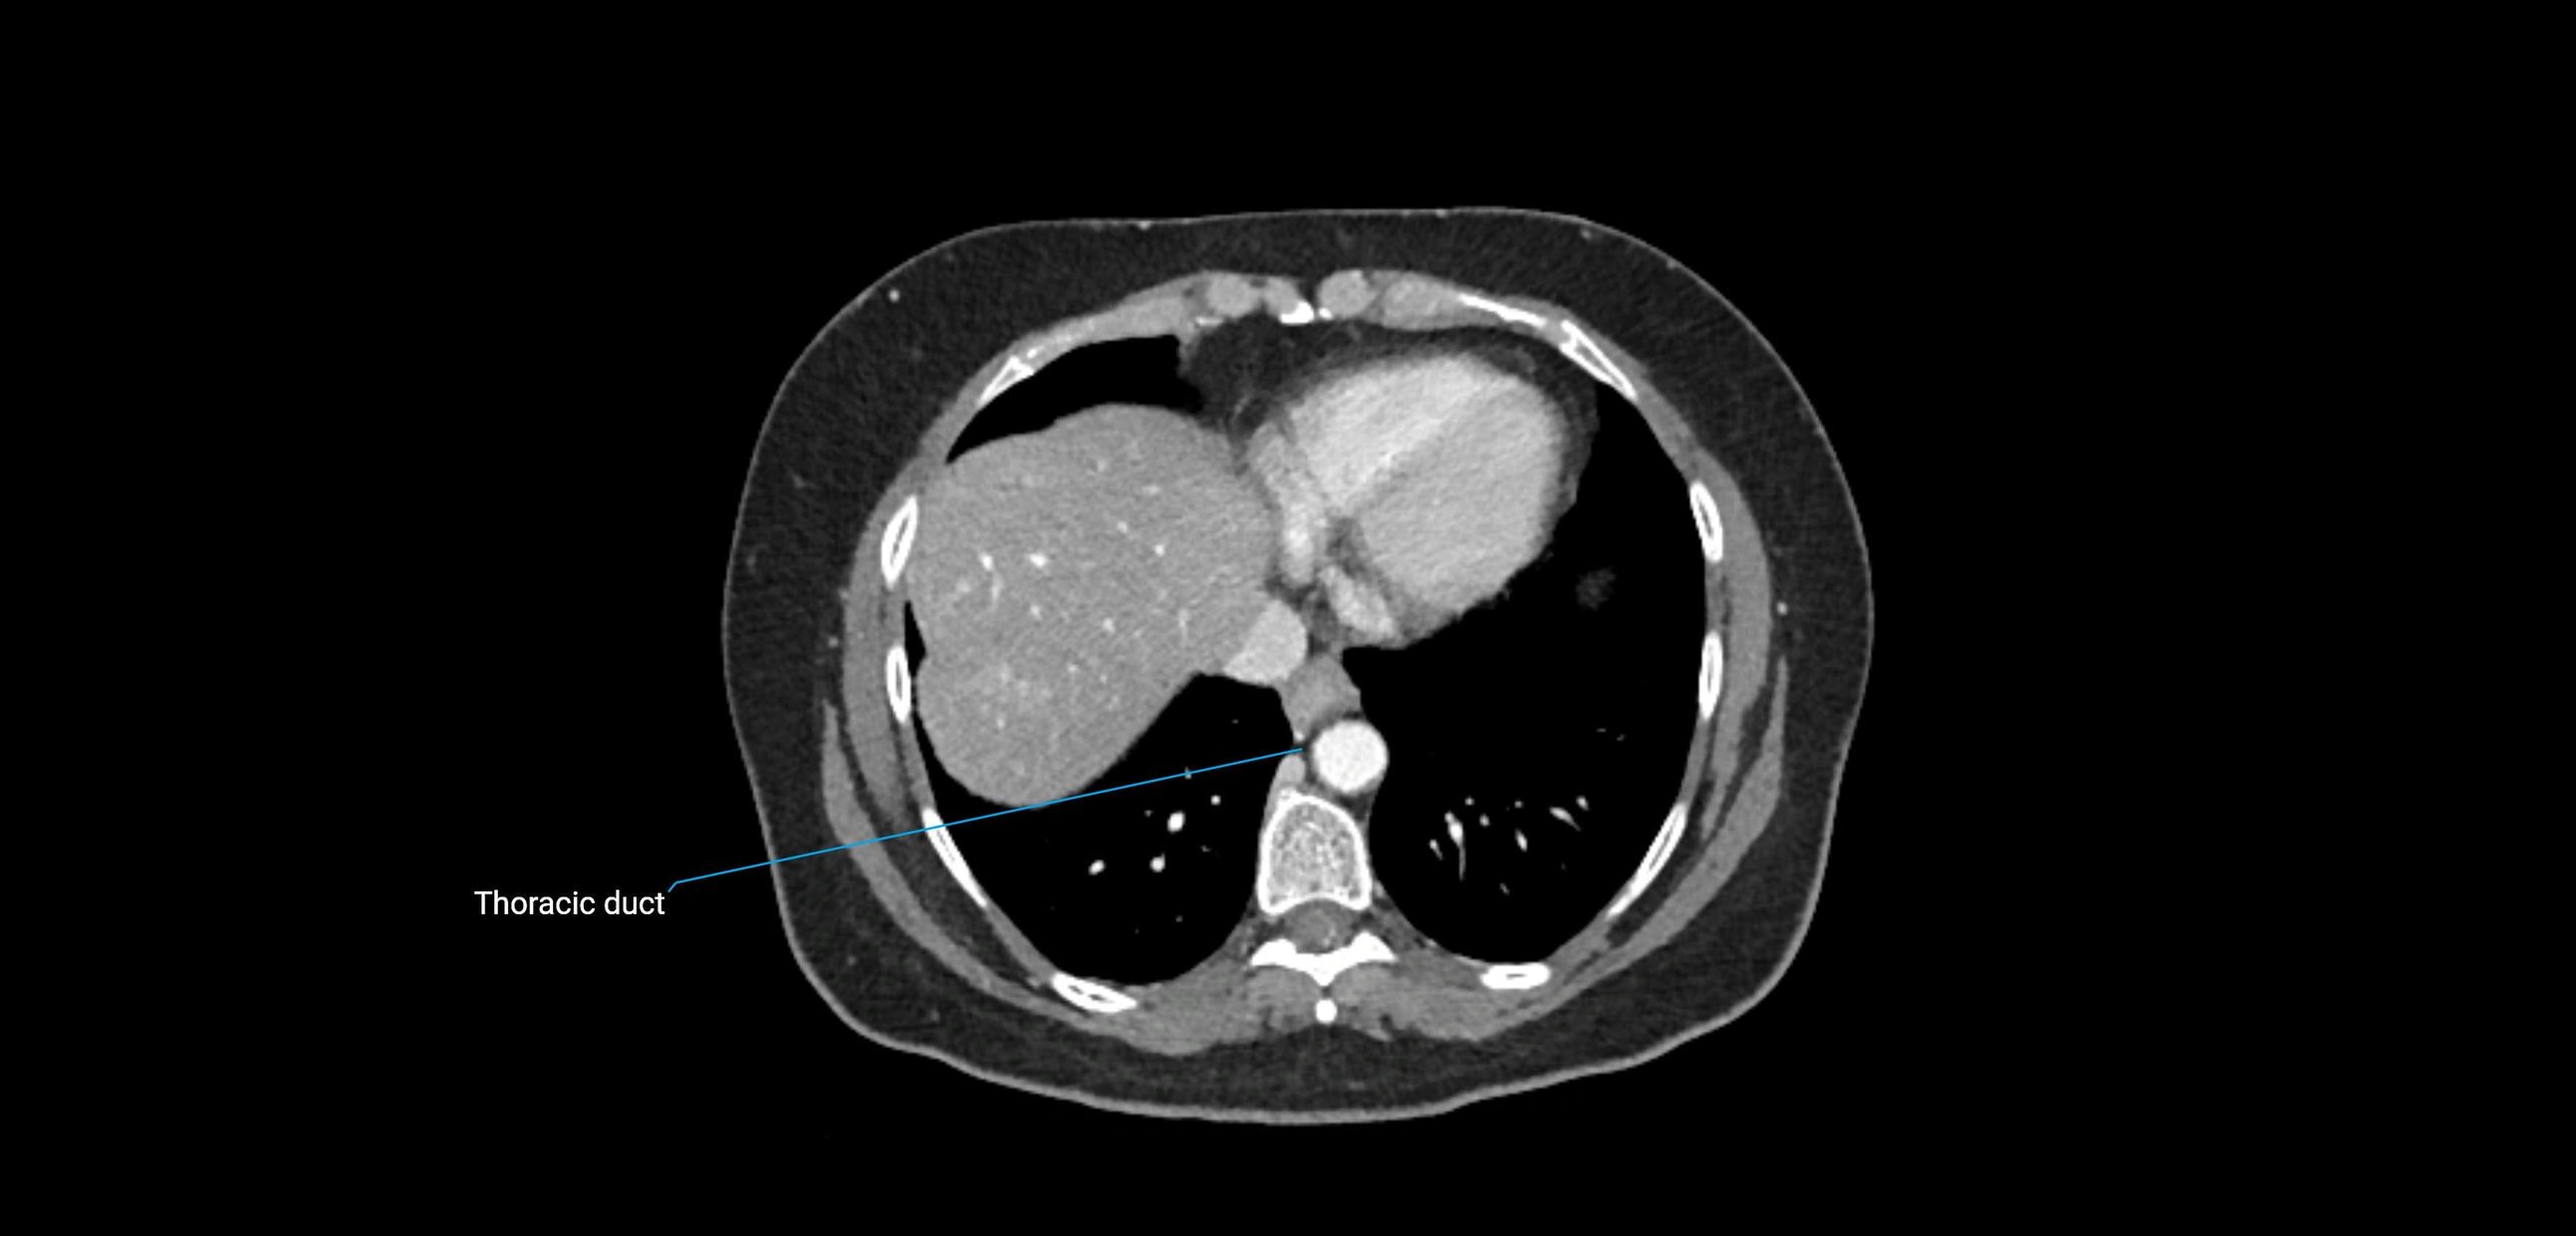

These nodes receive lymph from a wide range of abdominal and pelvic structures. Specifically, they drain lymph from the kidneys, suprarenal glands, gonads (testes/ovaries), uterus, uterine tubes, and pelvic organs, before converging into the lumbar lymphatic trunks, which terminate in the cisterna chyli → thoracic duct.

• Provide a major pathway to the cisterna chyli and thoracic duct

CT image

image